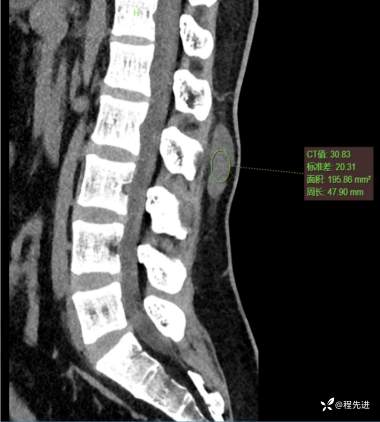

CT平扫:

矢状位重建: